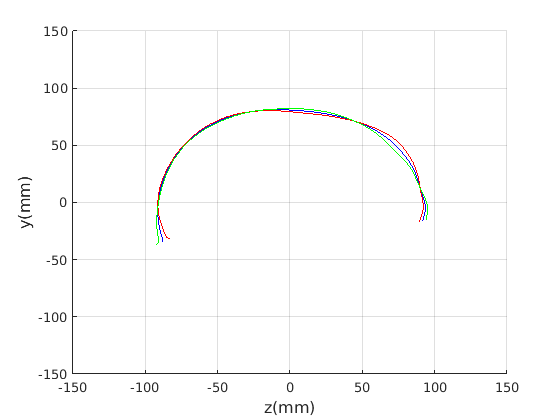

Figure 16 shows examples of the robust ellipse fit for four head profiles. The centre of the ellipse is used in a pose normalisation procedure where the ellipse centre is used as the origin of the profile and the angle from the ellipse centre to the nasion is fixed at -10 degrees. We call this Ellipse Centre - Nasion (ECN) pose normalisation and later compare this to GPA. The major and minor axes of the extracted ellipses are plotted as red and green lines respectively in Fig. 16.

|

Figure 17 shows all 100 profiles overlaid with the same alignment scheme. The median value of major ellipse axis and the ellipse centre-nasion angle differ by 3.6 degrees, so that when the nasion angle is fixed at -10 degrees, the median ellipse angle is -6.4 degrees (cf. -7.4 degrees with manual landmarking of the nasion). We noted regularity in the orientation of the fitted ellipse as is indicated by the clustering of the major (red) and minor (green) axes in Fig. 17 and the histogram of ellipse orientations in Fig. 18. For most people, the major axis of the ellipse is closely aligned with the y-axis (upright), and titled slightly forwards. A minority of heads (9%) in the training sample have their major ellipse axes closer to the vertical (these relatively tall and short heads are known as brachycephalic.) Ellipse axis clustering (relative to the fixed ellipse centre-nasion line) does not appear to be sharply defined. This is because many crania are close to circular in cross-section, making the orientation of these angles sensitive to small changes in shape from one person to the next. Note also the variation at the back of the head due to a variety of hair styles, some of which protrude from under the cap. We limit the region over which we model the cranial shape in order to crop this unwanted data out.